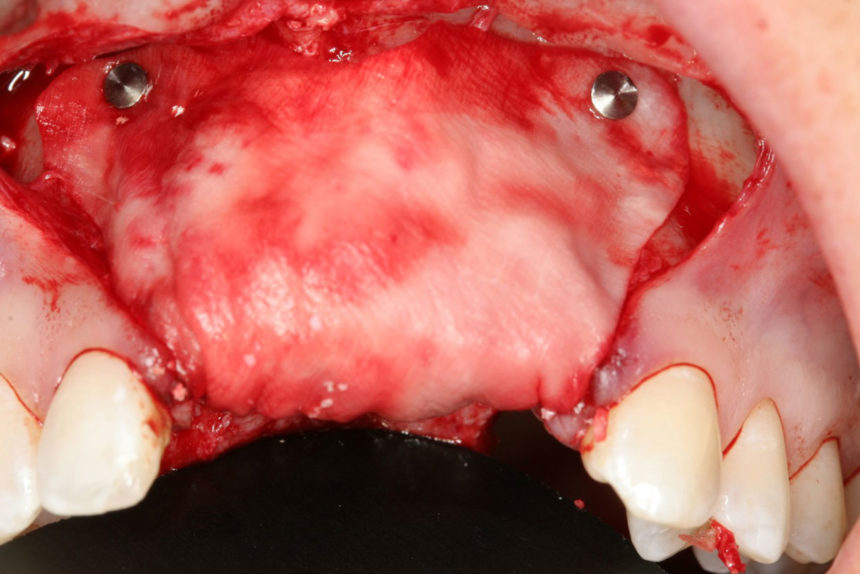

Οι συμμετέχοντες θα εξασκηθούν σε κάτω γνάθους χοίρων, με τα πιο σύγχρονα σχέδια εμφυτευμάτων, μικροχειρουργικά εργαλεία χειρός, bone tacks, βόεια υλικά πλήρωσης (filler) και απορροφήσιμες μεμβράνες και αυξητικούς παράγοντες με πλέγμα τιτανίου. Οι θεραπείες στις οποίες θα εκπαιδευτούν είναι:

3.Κάθετη αύξηση ακρολοφίας με κυτταροπλαστικές μεμβράνες PTFE με ενίσχυση τιτανίου, οστικές βίδες & ανάμικτο οστικό Ξενο/Αυτο-μόσχευμα σε αναλογία 1:1